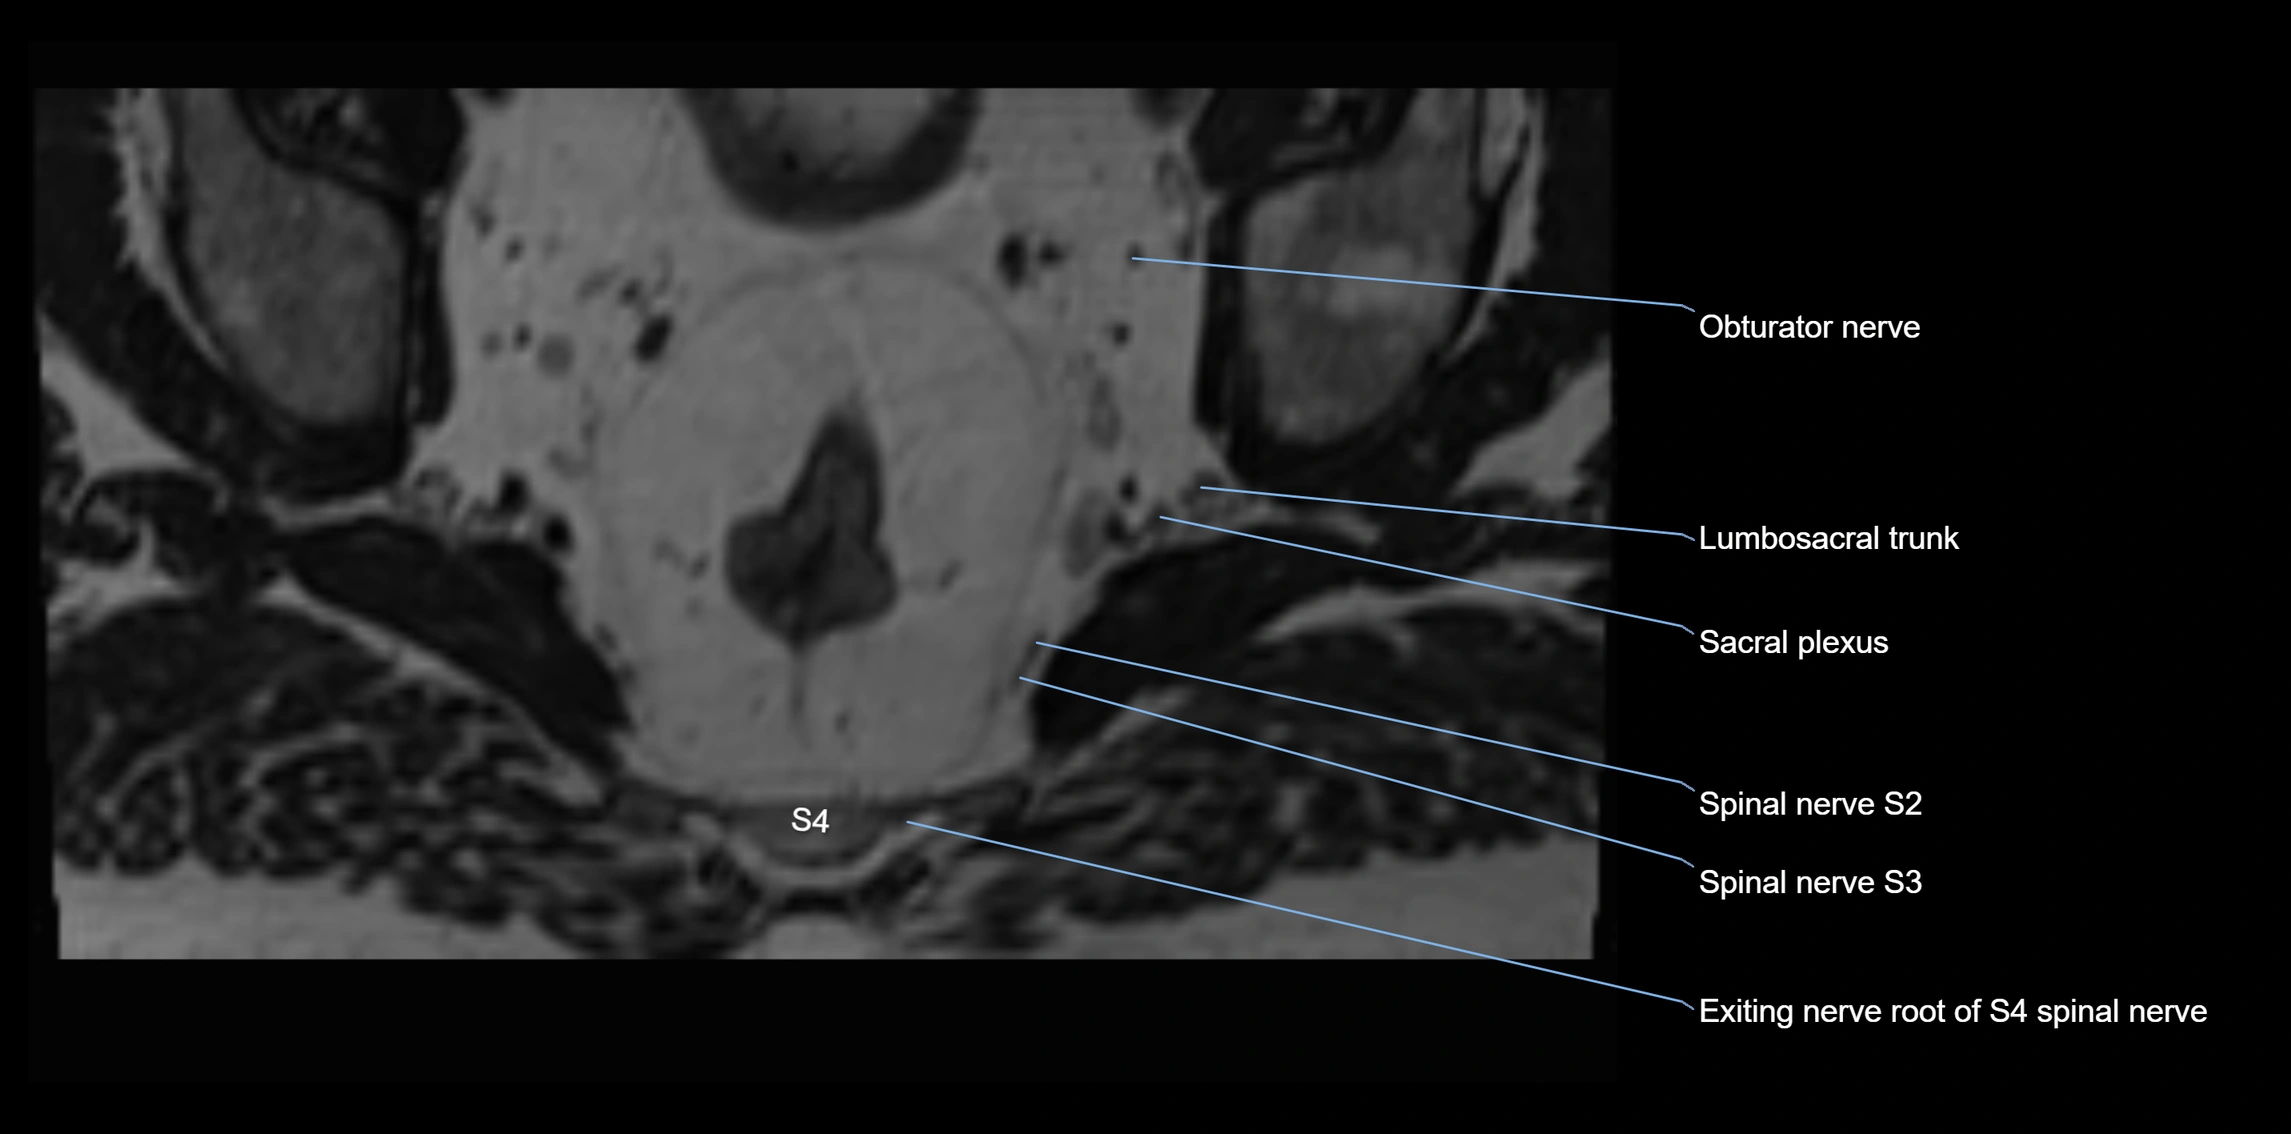

MRI Appearance

T1-weighted images:

• Nerve appears as a very thin low-to-intermediate signal intensity structure

• Surrounded by bright fat, aiding visualization

T2-weighted images:

• Nerve shows intermediate to mildly hyperintense signal compared to muscle

• Pathological involvement appears brighter

STIR (Short Tau Inversion Recovery):

• Normal nerve appears dark

• Inflamed or entrapped nerve appears bright hyperintense

T1 Fat-Sat Post-Contrast:

• Normal nerve enhances minimally

• Pathologic nerve (neuritis, entrapment, tumor infiltration) shows focal or diffuse enhancement

3D T2 SPACE / CISS:

• Nerve appears intermediate to mildly hyperintense compared to muscle

• Surrounded by bright fat or CSF, improving visualization

• Best sequence for mapping small pelvic nerves such as the anococcygeal

MRI image

image